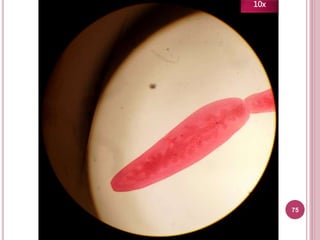

75

10x

Características

 Útero sacular

 Poro genital anterior

Tiene útero

sacular (¡Parece

un saco!)